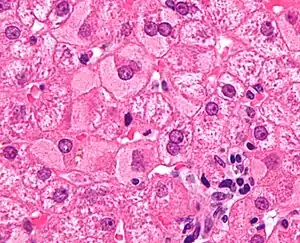

Ground glass hepatocytes

Micrograph of non-alcoholic fatty liver disease